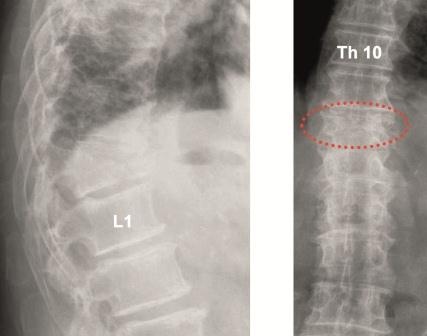

Kyphoplastie: Einfache osteolytische Metastasen können auch bei Hinterkantenbeteiligung üblicherweise bei entsprechenden Vorsichtsmaßnahmen mit der von uns bevorzugten Shieldkyphoplastie versorgt werden (Abb. 1a und b). Die reine Vertebroplastie erscheint uns in diesen Fällen zu riskant. Mit der Shieldkyphoplastie können wir die Osteolyse monopedikulär mit dem gebogenen Bohrer sehr gut adressieren und das Shield-Implantat genau dort platzieren. Perforationen im Shieldimplantat, aus denen der Zement gerichtet nach ventral austreten kann, stellen die Interdigitation mit der umliegenden Spongiosa sicher, wodurch die Stabilität erhöht wird.

Fixateur interne: Haben die Osteolysen bereits Frakturen verursacht und weisen die betroffenen Wirbelkörper relevante Deformitäten auf, hat sich die perkutane überbrückende Stabilisierung mittels Fixateur interne bewährt (Abb. 2a und b). Der betroffene Wirbel kann ggf. additiv kyphoplastiert werden. Angesichts der sich zumeist anschließenden Radiatio verzichten wir jedoch zumeist darauf. Die Schrauben können je nach Knochenqualität zur Erhöhung der Stabilität wie üblich auch zementaugmentiert werden.